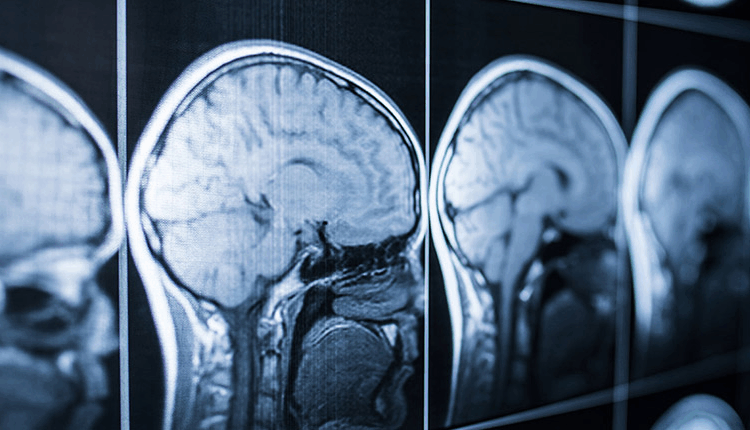

Bangalore: Abbott, the global healthcare company, announced the launch of its laboratory-based blood test to evaluate mild traumatic brain injury (mTBI), commonly known as concussions. The traumatic brain injury (TBI) test runs on Abbott’s Alinity i and Architect i1000SR laboratory instruments, which are available in major hospitals and laboratories such as Apollo, Hyderabad and Neuberg Supratech Laboratory.

The test offers a reliable result in 18 minutes to help clinicians quickly evaluate brain injury and triage mTBI patients. The diagnostic tool also helps eliminate the need for CT scans by up to 40% with a high degree of certainty eliminating wait time at the hospital and unnecessary exposure to radiation. The test measures two biomarkers in the blood – ubiquitin C-terminal hydrolase L1 (UCH-L1) and glial fibrillary acidic protein (GFAP) – that, in elevated concentrations, are correlated to brain injury.